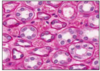

PROXIMAL TUBULES (PAS)

- highly coiled (sometimes with straight projection to medulla)

- prominent brush border and complex invaginations @ basolateral membrane dark pink

- extensive reabsorption here

- Na+ active transport with glucose (cotransporter - GLUT)

- take up protein and polypeptide by endocytosis

- cells contain lyzosomes which break down proteins before returning to circulation

- any small negatively charged protein can enter primary filtrate

PROXIMAL TUBULES 2 (PAS)

- this slide - straight portion of proximal tubule

- leads to loop of Henle

- if glomeruli present = cortex

- some project to medulla